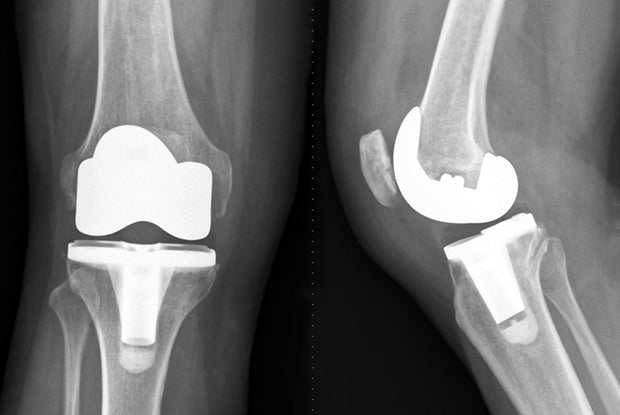

• 病人的膝關節僵硬、變形和活動能力下降,如果這非手術性的治療方法未能奏效,則可選用全膝關節置換的手術。全膝關節置換術是一種人工關節置換外科手術,是指切除機體已無法自行修復的關節面,用人工關節部件替代損壞的關節,矯正肢體力線,消除膝關節疼痛,維持關節穩定性,恢復膝關節功能的一種治療方法。